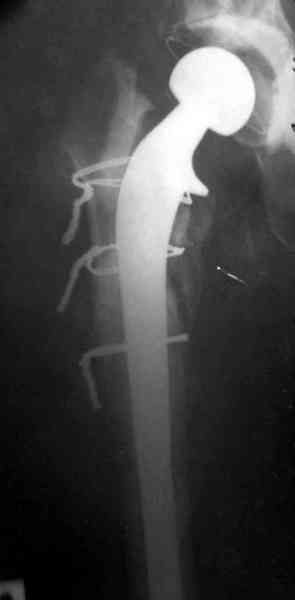

Для спейсера в бедро использовал старый длинный бедренний компонент меньшего диаметра, облепленный со всех сторон цементом с антибиотиком.

№3-6 снимки с осложнением

и последние снимки.